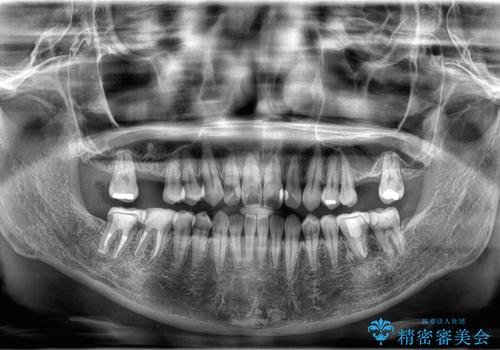

【歯牙移植】親知らずを移植して、インプラントを回避。

- 銀歯の下が大きな虫歯になり、保存困難のためその後の治療計画について悩まれていた患者様です。

患者様と相談し、親知らずを用いて歯牙移植を行いました。

移植歯はアンキローシス(歯と歯槽骨の間の歯根膜がなく、歯の根と骨が結合している状態)するリスクがあります。

アンキローシスを避けるため、術中や術後管理に注意が必要です。